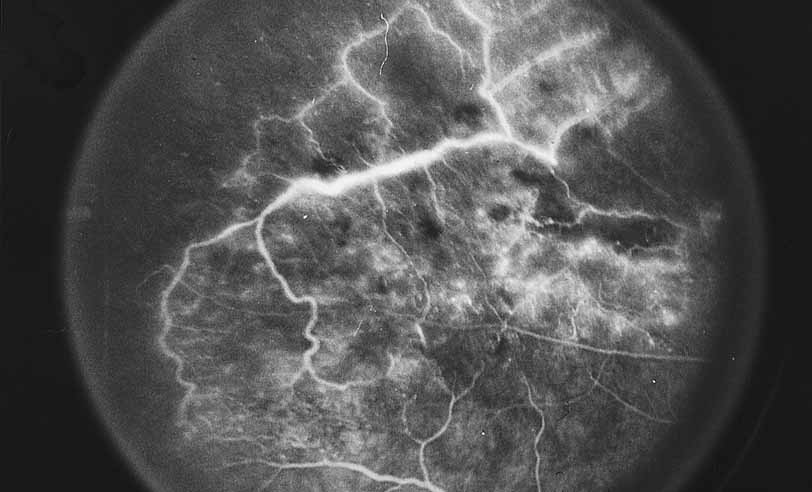

Fig. 1 Serpiginous choroiditis. Early frame of the fluorescein angiogram shows hypofluorescent and hyperflourescent patches extending outward from the optic nerve in a serpiginous pattern (Courtesy of Joseph Michaelson).

Fig. 2 Serpiginous choroiditis. Late frame of the fluorescein angiogram shows extensive staining of previously hypofluorescent zones, with continued hypofluorescence, characteristic of the acute phases of serpiginous choroiditis (Courtesy of Joseph Michaelson).